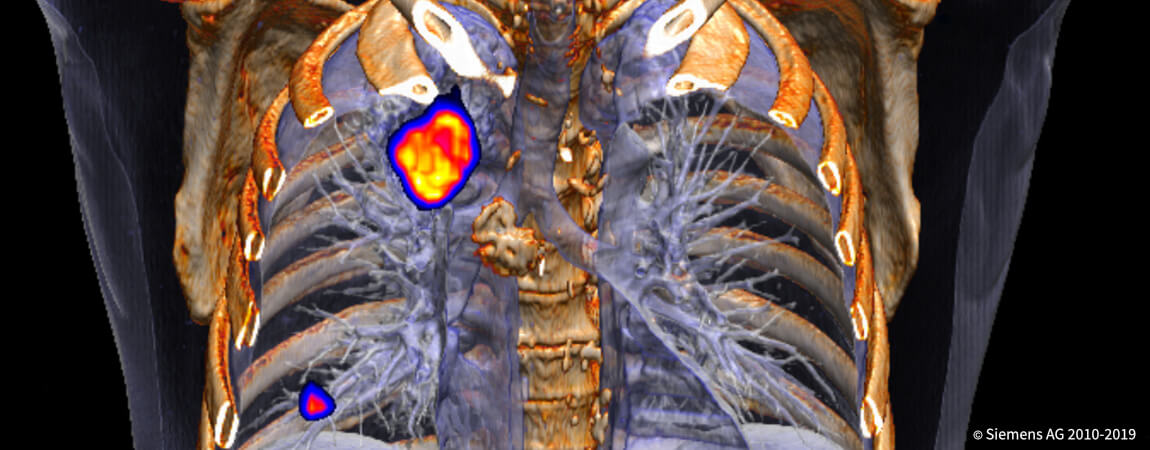

- _Все методы томографии

- _Ядерная медицина: сцинтиграфия скелета, ПЭТ-КТ